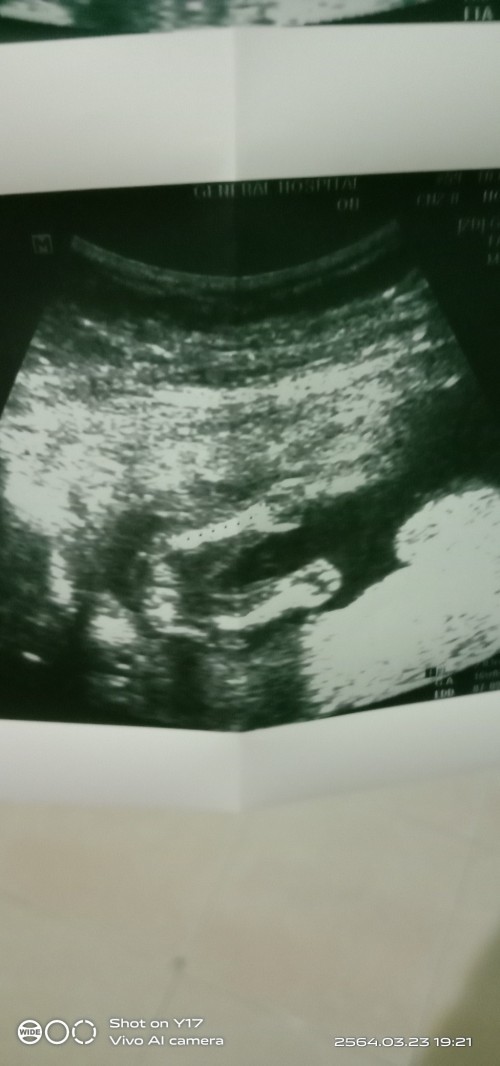

ใบซาวเพศลูก😊😊

ซาวด์ตอน19วีคจ้า ผู้หญิงจ้า😊

อายุครรภ์ 19สัปดาห์ เพศชายค่ะ

16 สัปดาห์ หนูเป็นลูกสาวค่ะ

ลุงหมอบอกชายจ้าา 17w

17 สัปดาห์ ชาย 100% เลยค่าา

ซาวตอน 16 w ได้ลูกสาวค่ะ

ซาวตอน19w ได้ลูกสาวจ้า